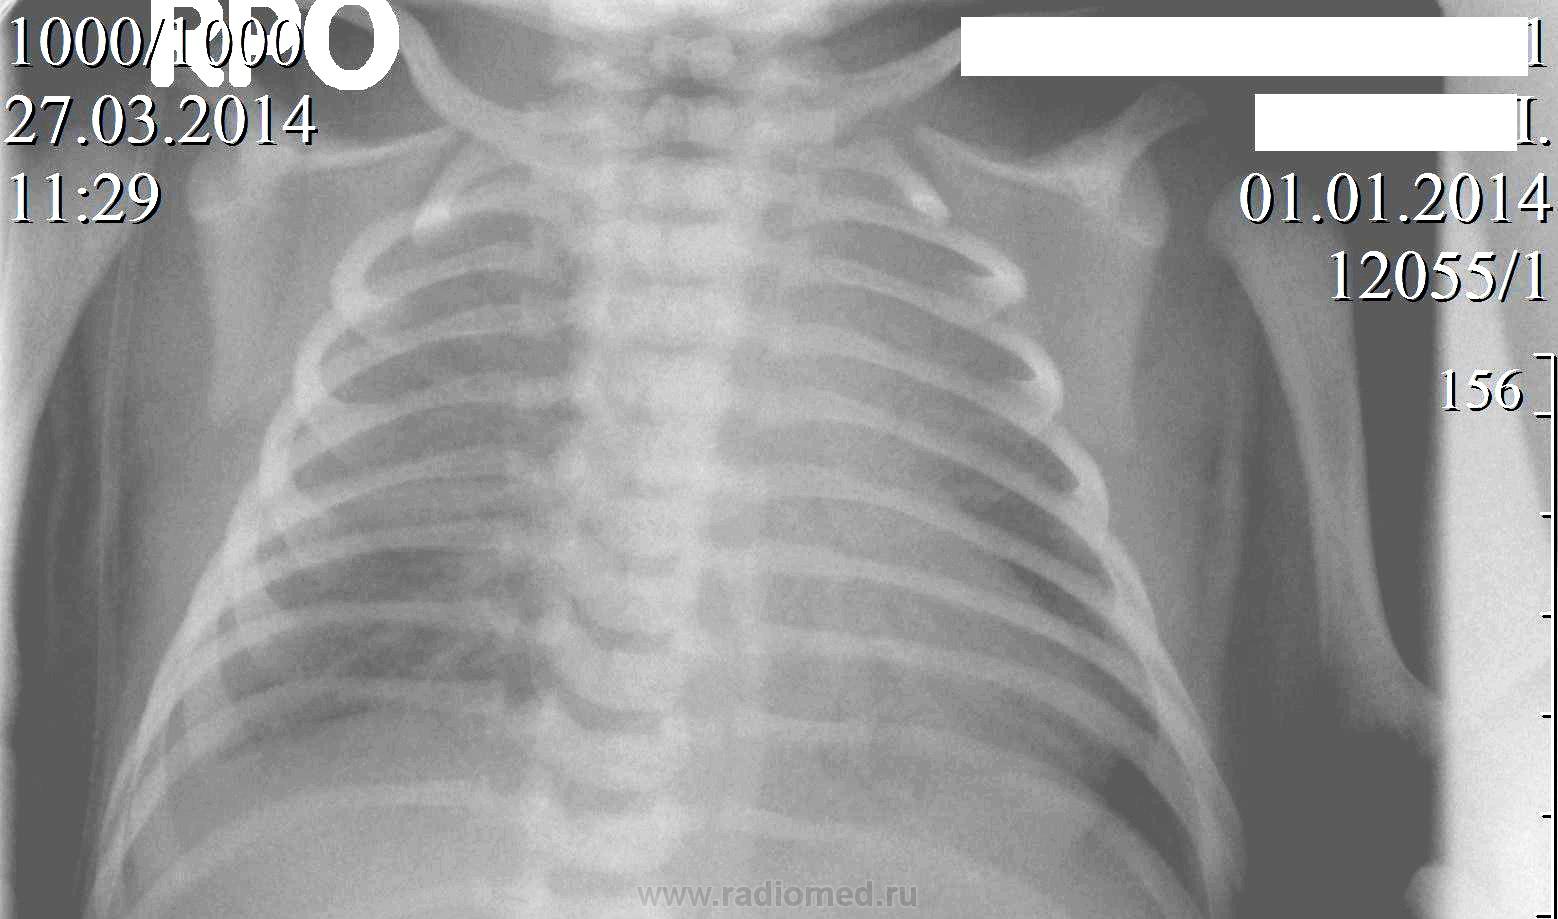

Новорождённый.  Направлен с подозрением на врождённый порок  сердца.R-графия  лёгких  в прямой проекции.

Возникли вопросы по оценке  тяжистой тени слева на фоне тени сердца и справа в среднем поле.

качество не позволяет увидеть ничего

Я не сосем понял, что это было, но  на контрольных R-граммах сегодня ( представленный снимок выполнен вчера и были назначены снимки в  прямой, левой и правой боковых проекциях) нашёл  только нитевидное  уплотнение малой междолевой плевры справа.

Уважаемый коллега! Ну точно ни Х.орошо ничего не видно. Одно видно- легкие воздушны, сердце на месте и без оказий. Остальное в процессе.smiley Т.е. динамика решает тут все.

Не факт, что с первым вдохом легкие расправляются на сто процентов.

Тень слева, очевидно, была экстракорпоральной, если на контрольном снимке ее нету. Может что-то забыли под младенцем. Справа, с учетом динамики, небольшой выпот в междолевой плевре.

R-грамммы в боковых прокциях были сразу назначены и на следующий день выполнены, только я на них ничего не увидел, кроме уплотнения междолевой плевры справа по малой и главной щели в базальном отделе.

Может быть, но она скорее эта  тень производила впечатение анатомического образования-  возможно, какого-то сосуда( только какого?).